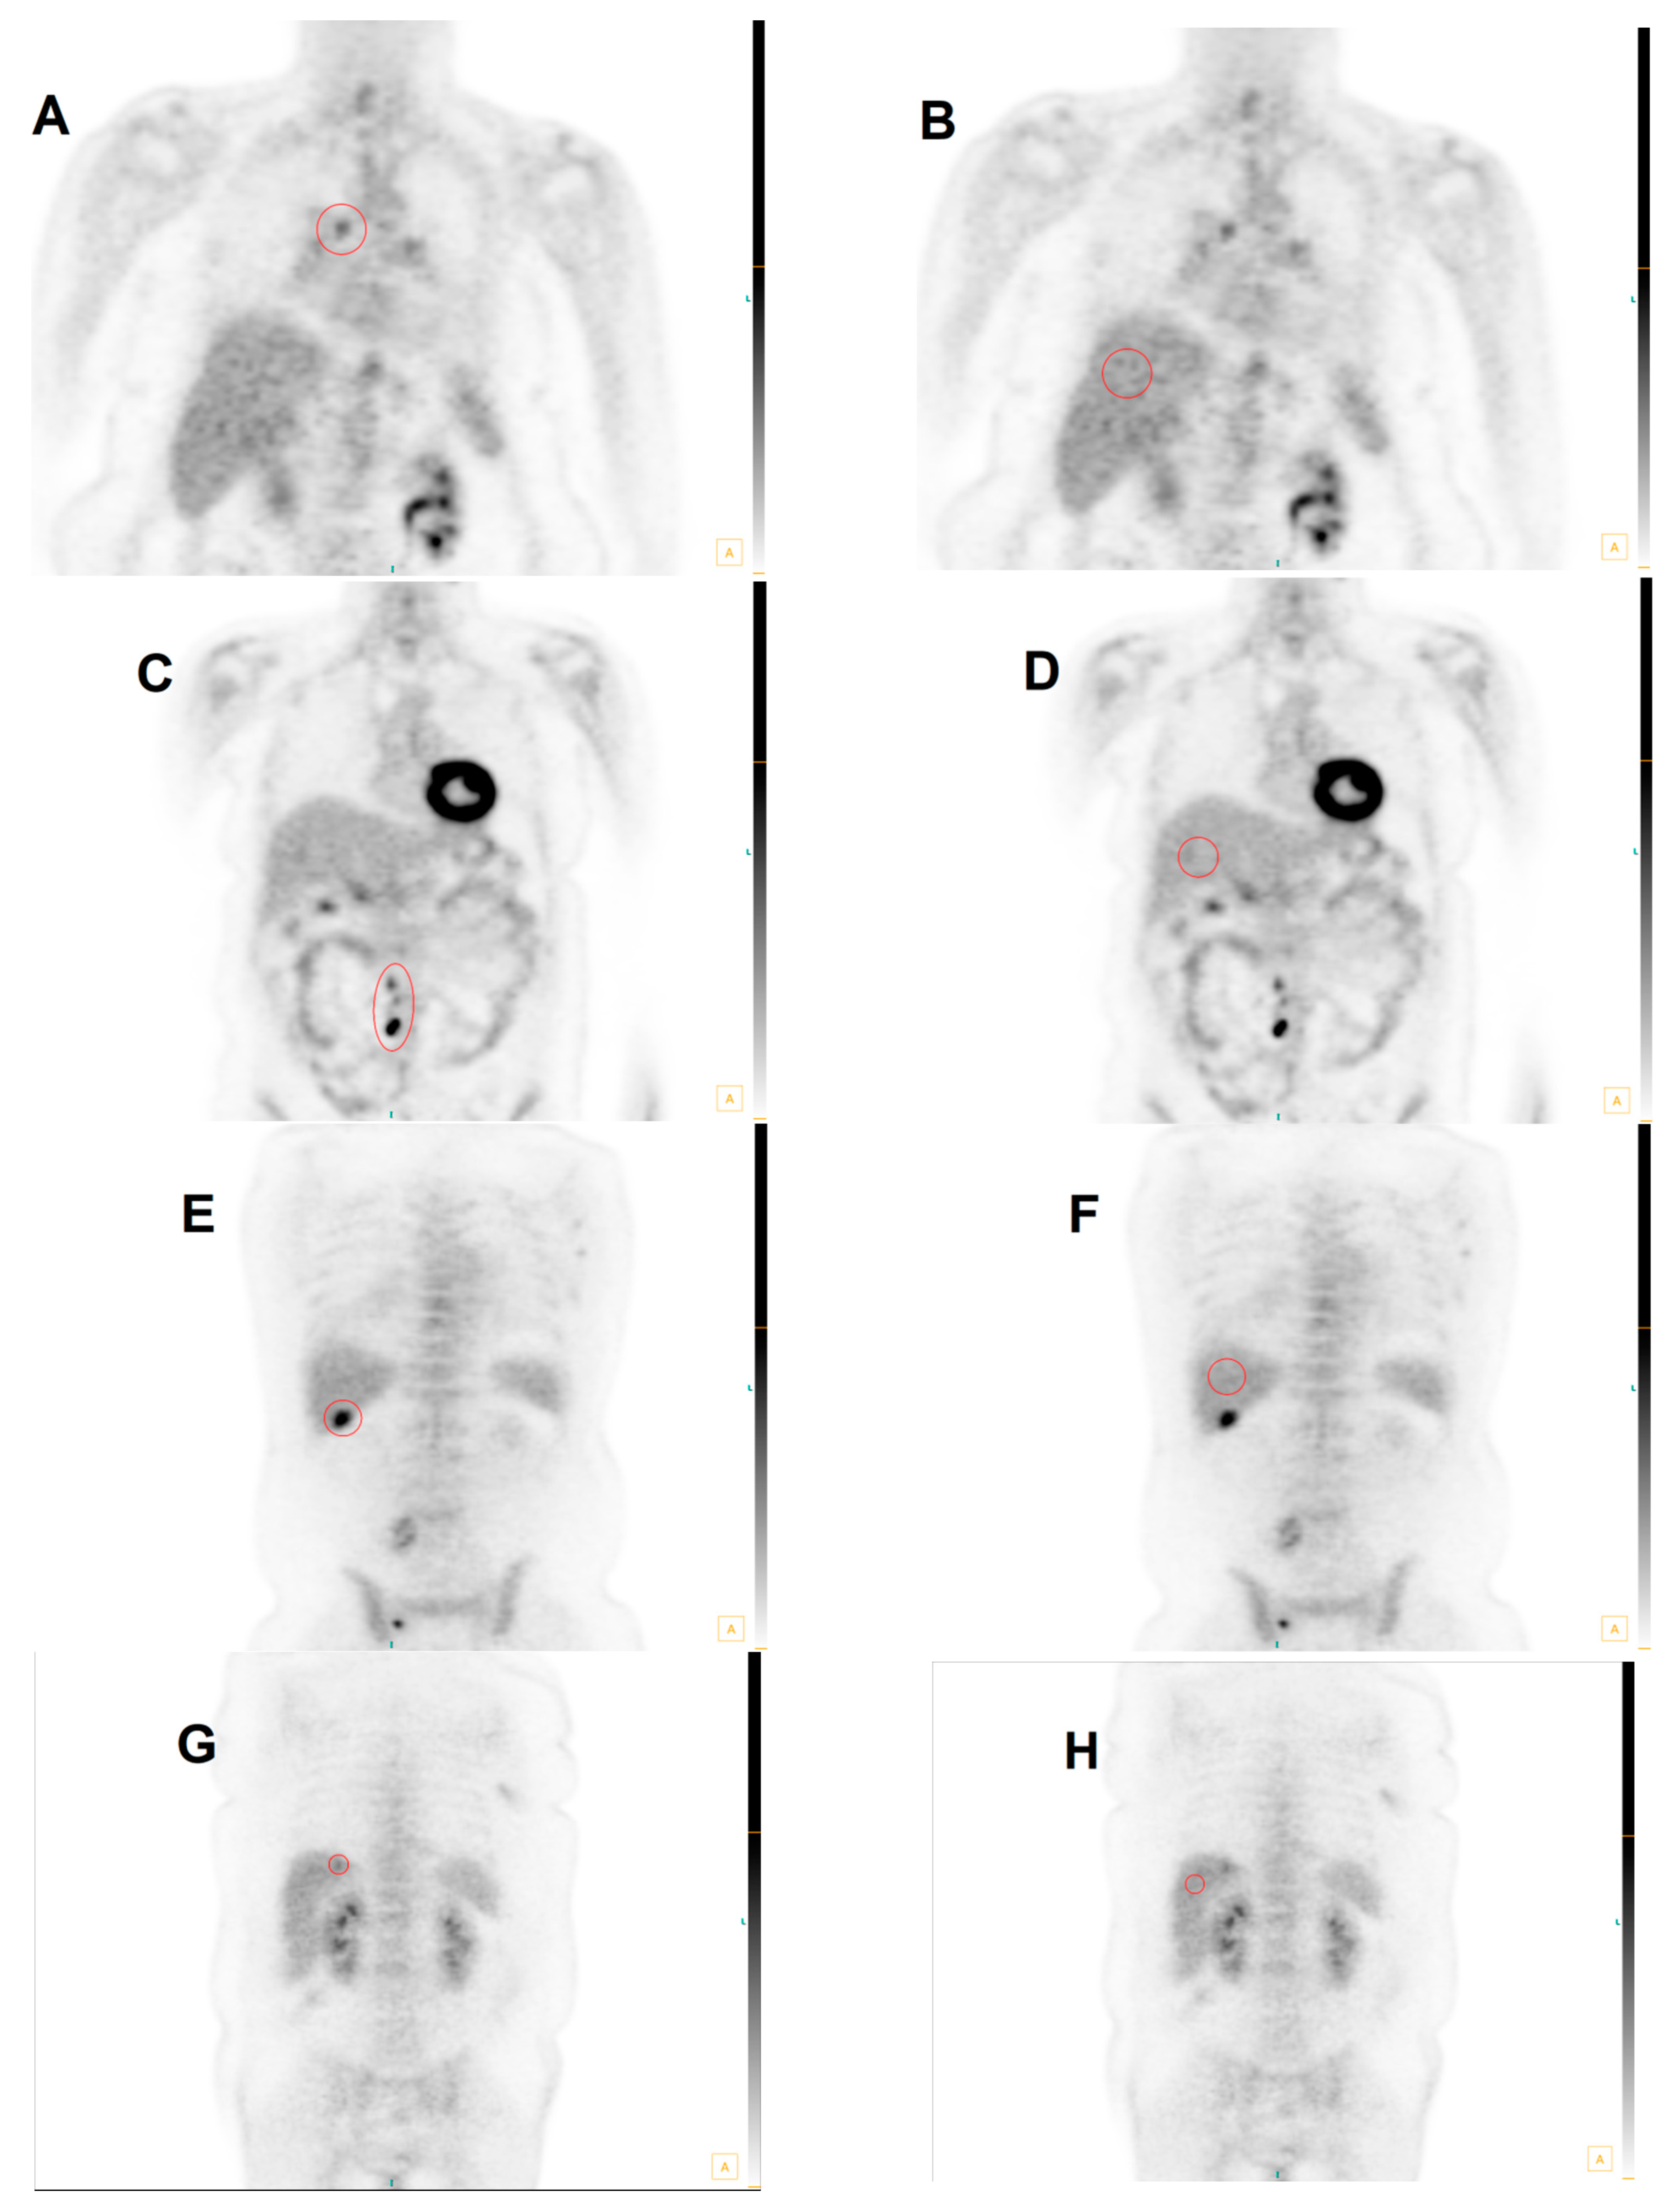

3.2. Group 1: MHLN Lung Cancer Cohort

3.3. Group 2: ETLN Cohort

3.4. Group 3: Hepatic Parenchymal Colorectal Carcinoma Cohort